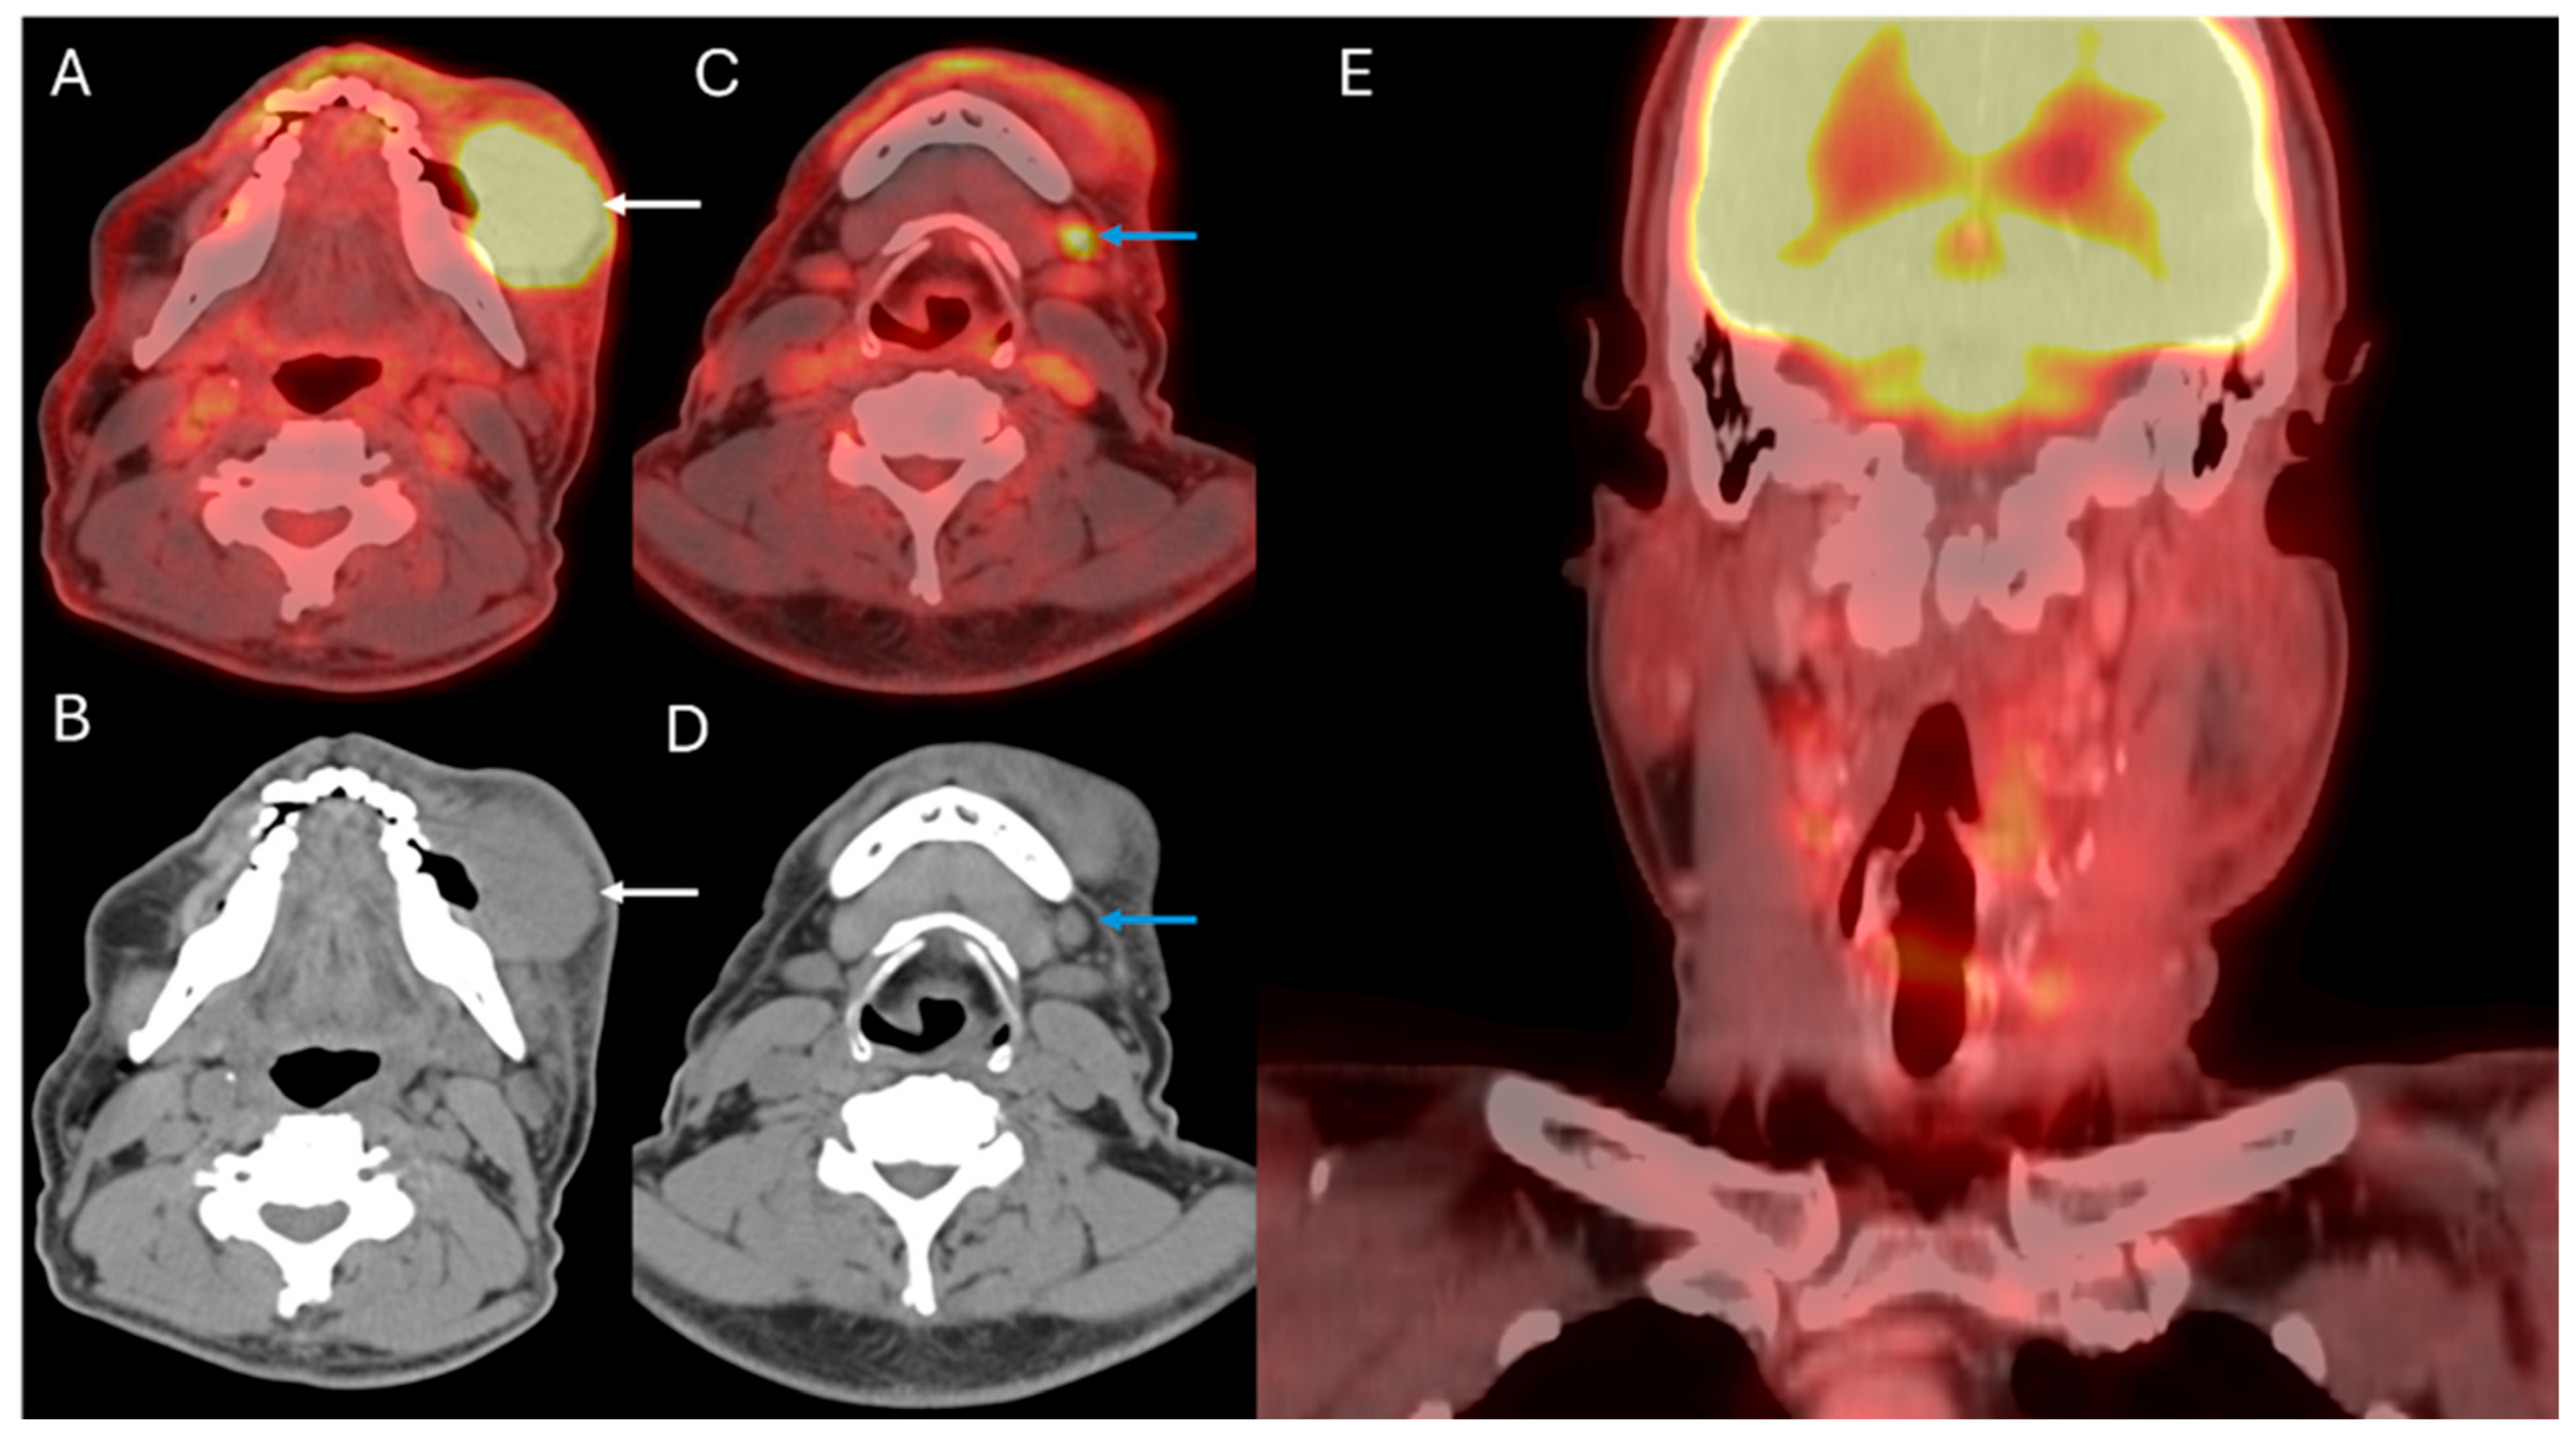

4. Staging of Cervical Nodal Metastases

5. Distant Disease Detection